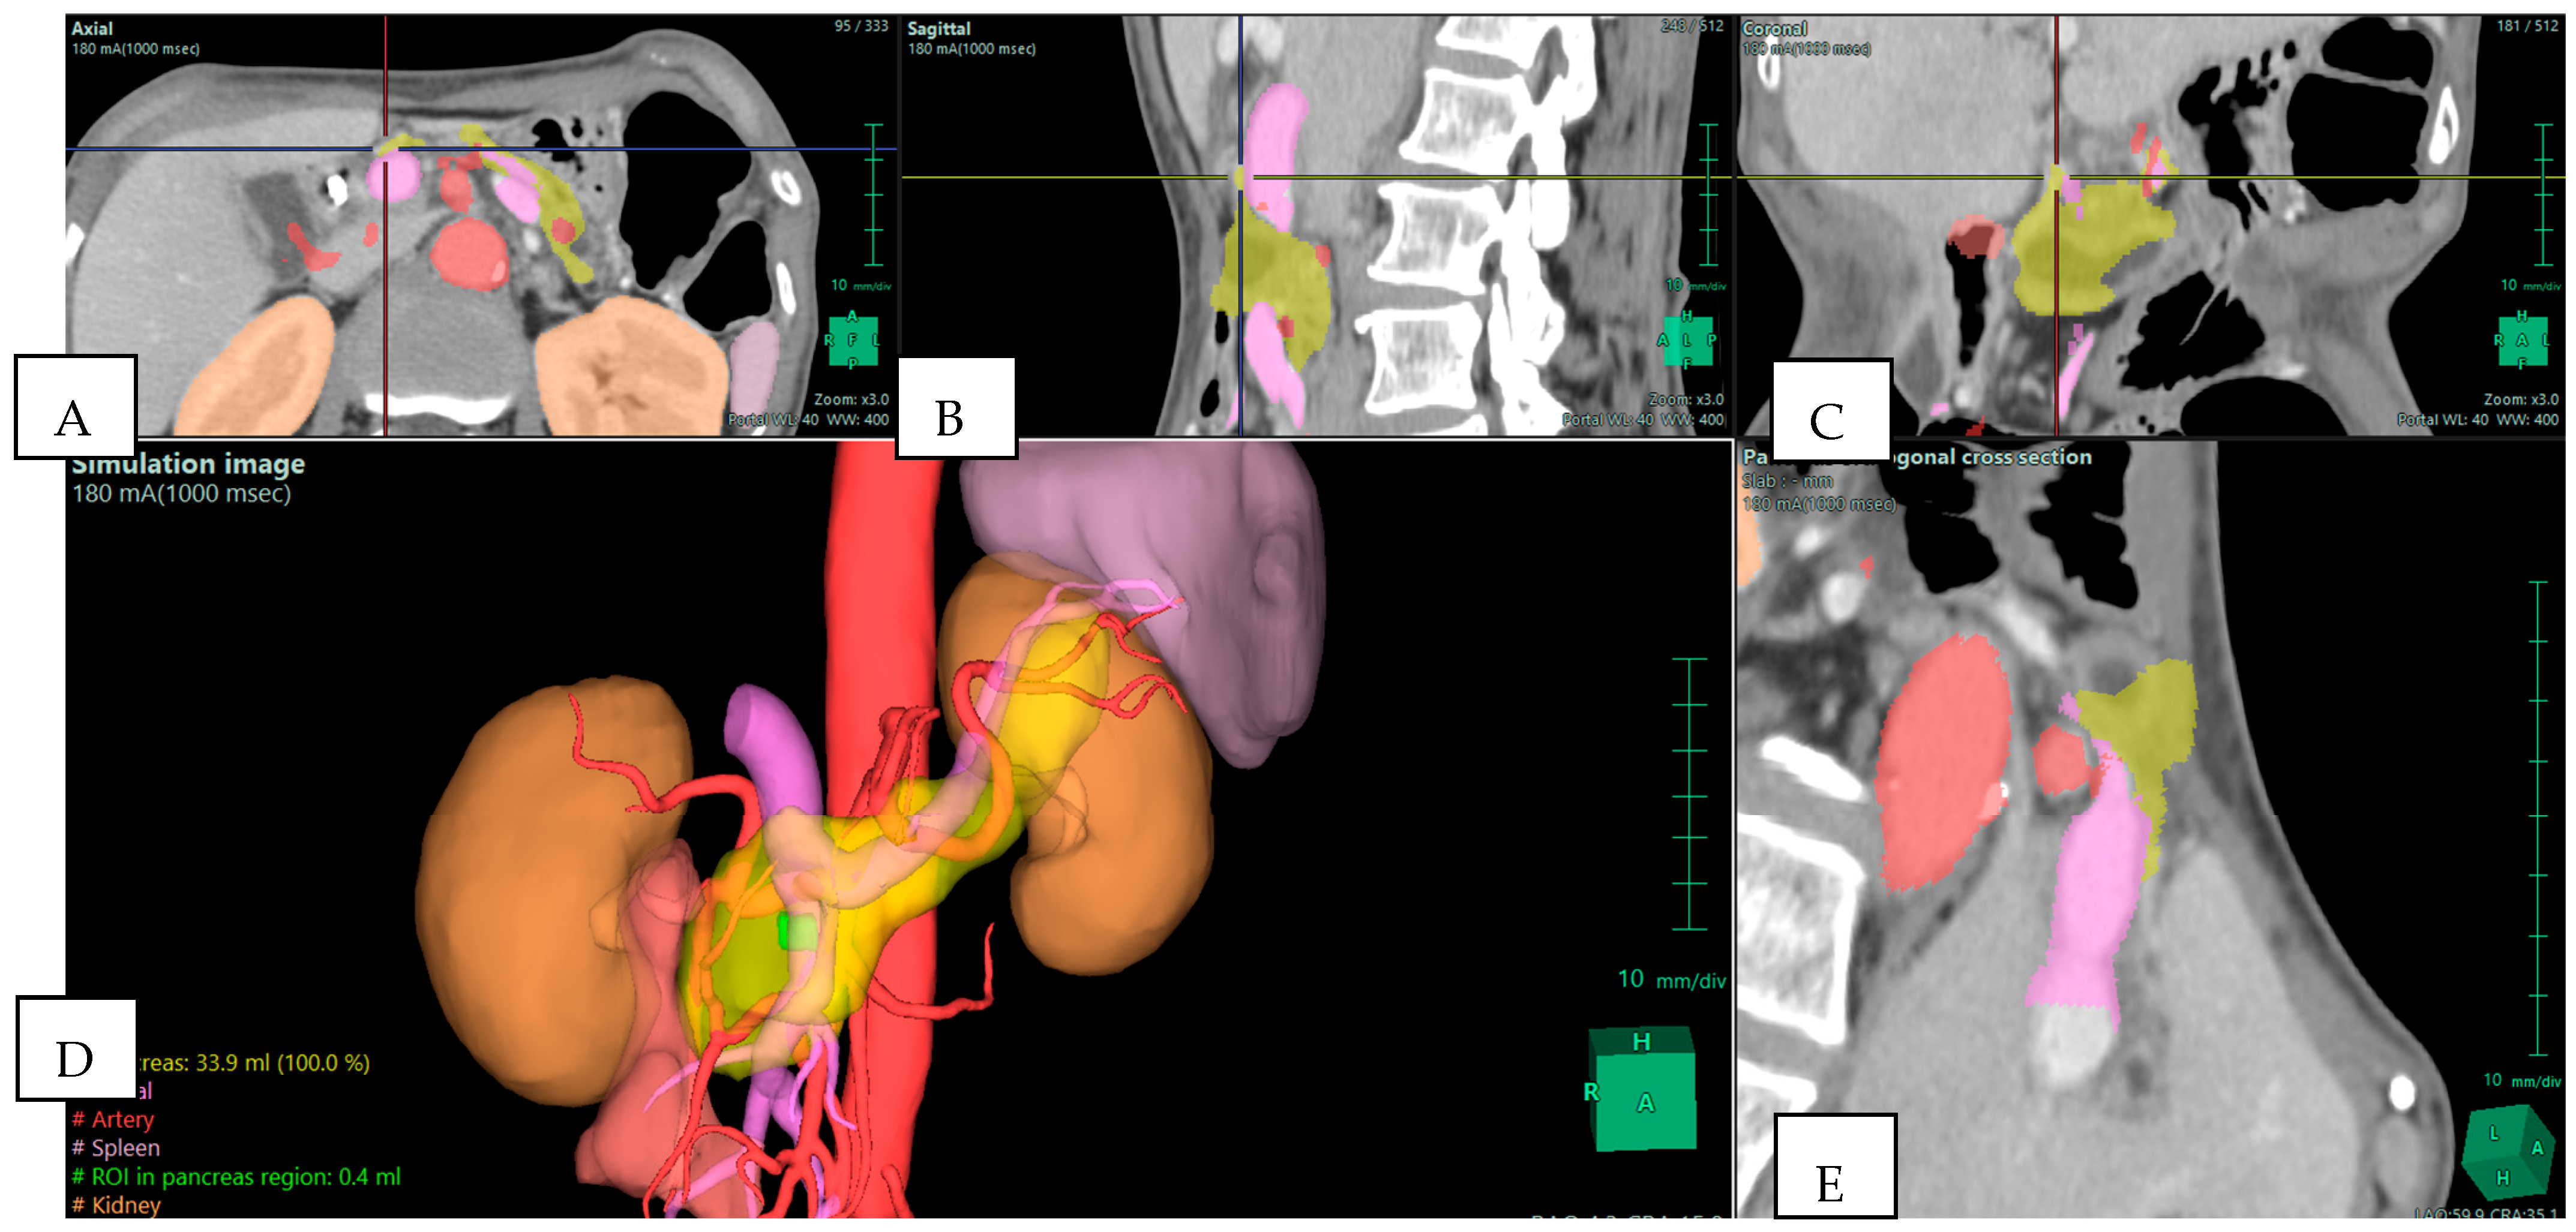

Isolated reports also highlight the ability of 3D reconstructions to reveal details that traditional imaging may miss (Figure 2). Templin et al. described a case in which interactive 3D vascular reconstruction revealed a rare Bühler’s anastomosis, not visible on standard CT [7]. This information, confirmed during surgery, changed the operative strategy and likely prevented serious complications. Vicente et al. went further, showing that 3D vascular models achieved nearly 100% sensitivity and specificity in predicting vascular invasion in pancreatic cancer, outperforming CT and MRI [3]. This level of accuracy allows for better planning of vascular resections and helps avoid unnecessary or unsafe procedures.

Figure 2. Preoperative Planning of Uncinate Process Pancreatic Adenocarcinoma (PDAC) in a 69-year-old Woman. Multiphase CT scan with 3D volume rendering shows the tumor (green) arising from the uncinate process and abutting the superior mesenteric vein (SMV)/portal vein (PV) confluence (purple). Note the presence of an aberrant right hepatic artery originating from the superior mesenteric artery (SMA) (red). (A) Axial plane; (B) sagittal plane; (C) coronal plane; (D) 3D reconstruction—simulation image; and (E) pancreas orthogonal cross section. Images derived from anonymized clinical datasets from our institution.